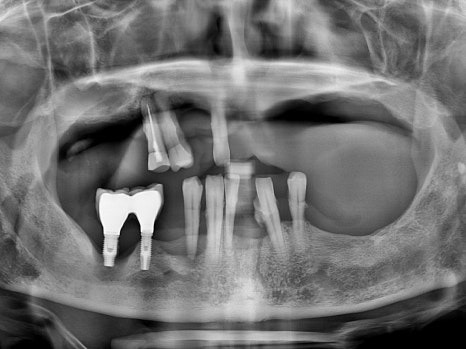

치료 전 파노라마

오래 전 임플란트 치료를 하였지만

염증으로 인해 모두 빠져버린 상황에서

오른쪽 하나만 닿는 어금니로 식사를 하고 계시던 중,

위쪽 치아마저 아파지면서

식사가 아예 불가능하게 되었다고 하셨습니다.

남은 치아는 모두 발치해야 하는 상황,